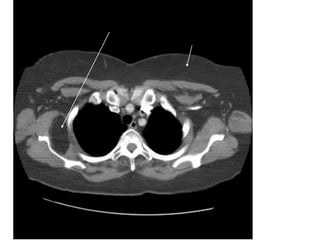

Figure 30a. Hạch bình thường vùng rốn phổi 2

bên.

40

Figure 30b. Hạch bình thường vùng cạnh động mạch liên thùy 2

41

Figure 30c. Hạch bình thường vùng thùy giữa (P) và thùy

lưỡi (T).

42

Figure 30d. Hạch bình thường thùy dưới 2 bên.

43

Figure 31. Chỗ chia đôi của đm thùy lưỡi và thùy